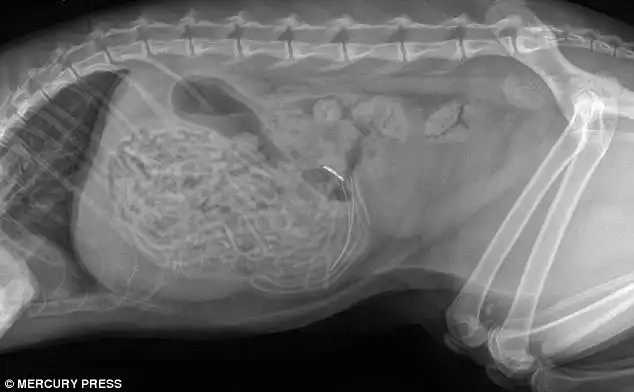

Годовалый кот, который съел 30 резинок для волос

А вот и они, извлеченные из его живота